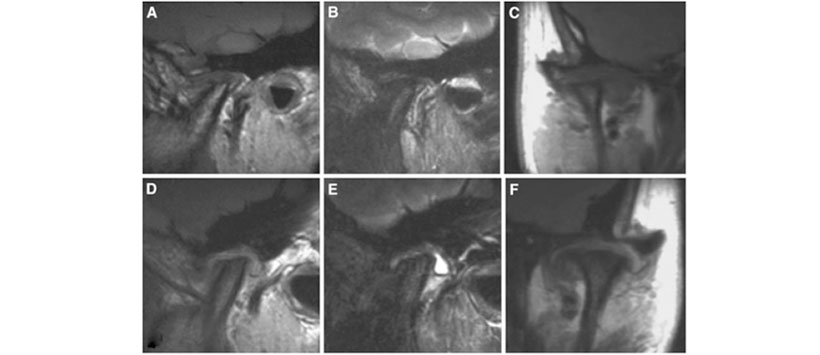

En las imágenes coronales, se observó una marcada proliferación sinovial, que mostró una mejora de contraste homogénea en la ATM en ambos lados. En los exámenes de IRM tercero y cuarto, se confirmó que la destrucción ósea había progresado en ambos lados. En particular, en el cuarto examen de MRI a los 2 años después de la visita inicial (Fig. 3), la estructura normal del cóndilo derecho casi había desaparecido.